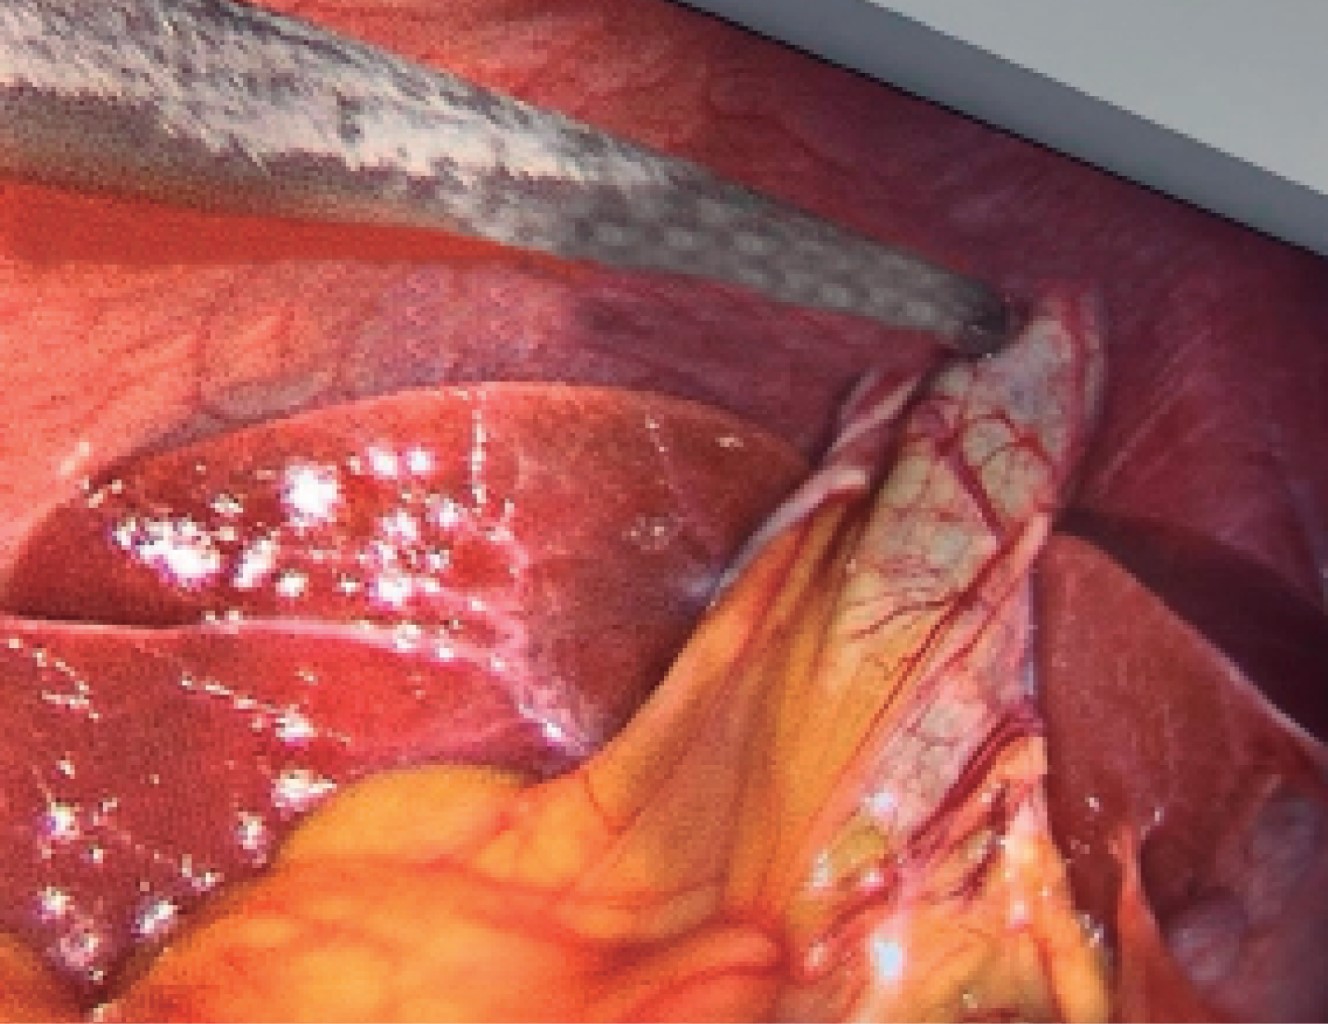

The histopathological diagnoses of the 60 operated patients were compatible with acute chronic cholecystitis and coincided with adhesions of the greater omentum, duodenum, transverse colon to Hartman's pouch, or body, or gallbladder fundus or that the greater omentum completely covered the entire gallbladder as shown in Figures 4, 5 and 6.

Figure 4